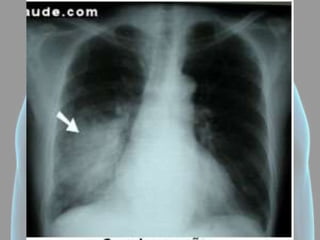

Pneumotórax

• Hipertransparência

(presença de ar no

espaço pleural);

• A pleura visceral

delimita o pneumotórax;

• Não haverá trama

vascular na área;

• Mediastino direcionado

para o lado oposto.

Pneumotórax • Hipertransparência (presença dear no espaço pleural); • A pleura visceral delimita o pneumotórax; • Não haverá trama vascular na área; • Mediastino direcionado para o lado oposto.